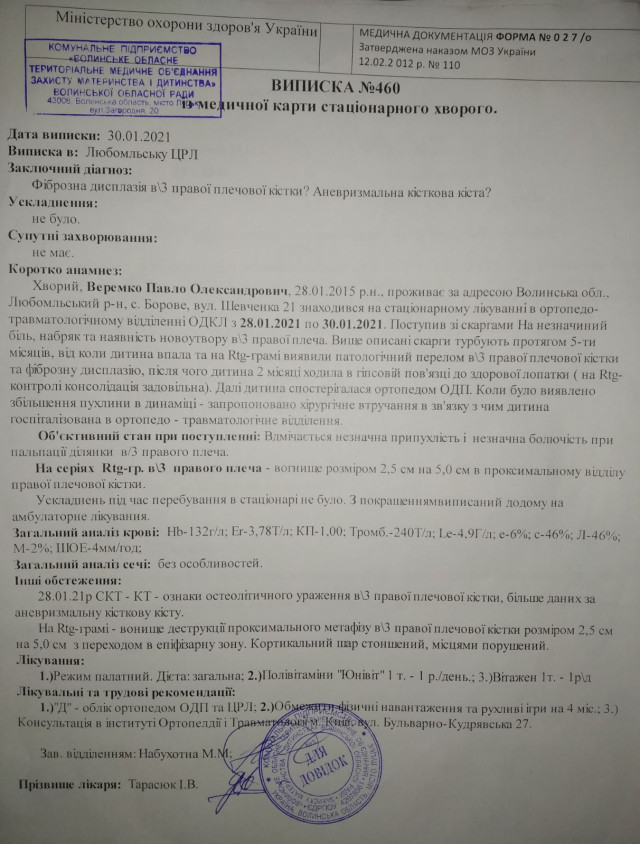

«Так сталося, що син упав і зламав ручку, – ковтаючи сльози, розповідає мама хлопчика Сніжана. – Нам встановили діагноз фіброзна дисплазія плечової кістки. І через цю пухлинку в Павлика – підвищена ламкість кісток. Із цим діагнозом нас скерували до Луцька. Оскільки був перелом, синочкові наклали гіпс, у якому він проходив два з половиною місяці».

Обласні спеціалісти порекомендували спостерігатися й далі. А вже коли робили контрольні знімки, з’ясувалося, що пухлина почала збільшуватися. Дитині встановили інший діагноз – аневризмальна кісткова кіста.

Зараз ручка в дитини спухла й почала боліти. Пухлина збільшилася й тепер вона 2,5 на 2,7 см і має відростки по 4 мм.